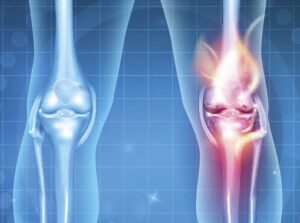

Artrose do Joelho

Uma doença comum que afeta os joelhos e desgasta a cartilagem é conhecida como artrose, um processo de desgaste da cartilagem que reveste as extremidades

Uma doença comum que afeta os joelhos e desgasta a cartilagem é conhecida como artrose, um processo de desgaste da cartilagem que reveste as extremidades